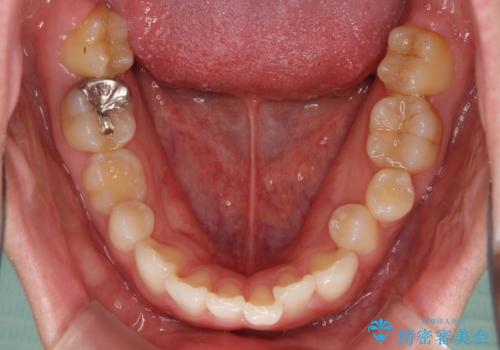

- 咬み合わせと前歯のデコボコを気にして来院された患者様です。

前から5番目の永久歯が3本欠損しており、乳歯が残存している状態でしたが、インビザラインでも十分に対応可能と判断し、インビザラインにて矯正治療を行うこととしました。

右下の残存している乳歯は萌出しきれておらず、全く咬み合っていない状態であり、インビザラインにて移動できない可能性があるため、ワイヤー矯正の併用も念頭に置いて治療を開始しました。